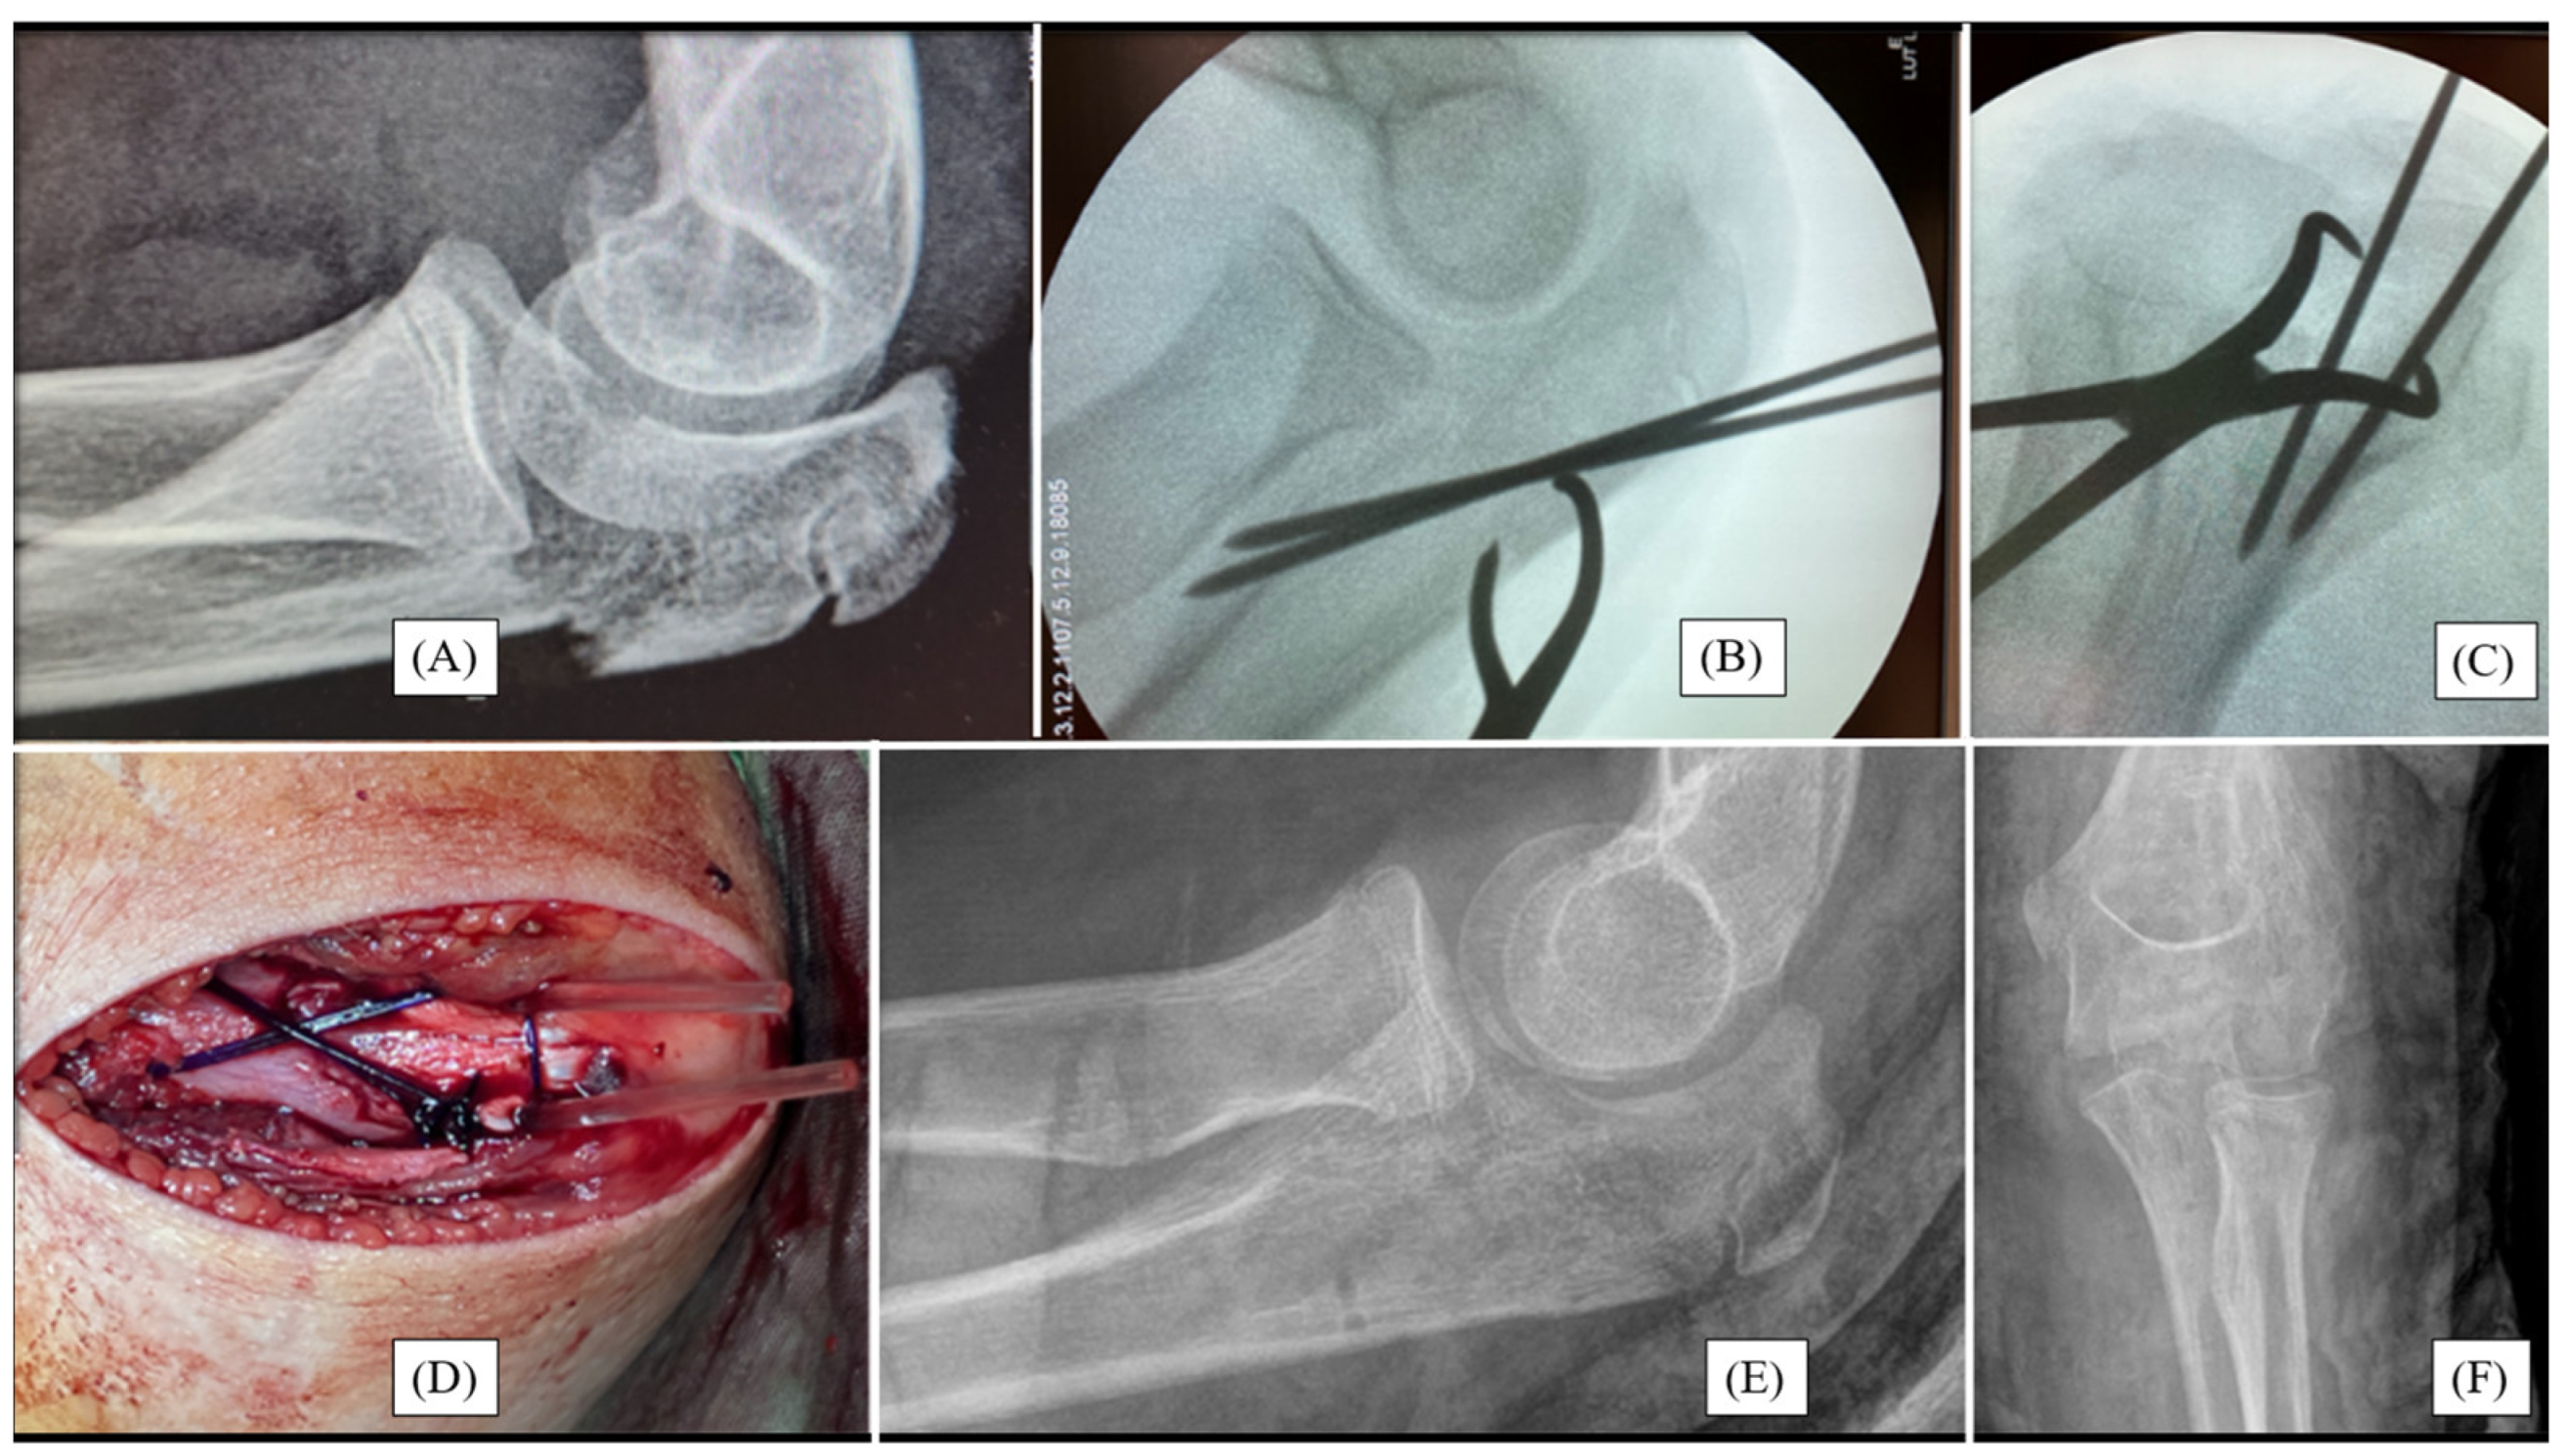

3.1. Case 1